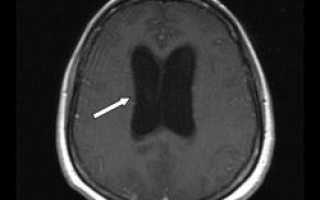

Диагностирование заболевания

Определить наличие синдрома крайне сложно, а установить диагноз с абсолютной уверенностью практически невозможно. Врожденный синдром определяется корректностью функционирования рефлексов и размерами окружности головы. Для подтверждения или выявления его у детей и взрослых проводятся обследования глазных сосудов, томографические исследования, ультразвуковая диагностика, а также пункция спинномозговой жидкости.